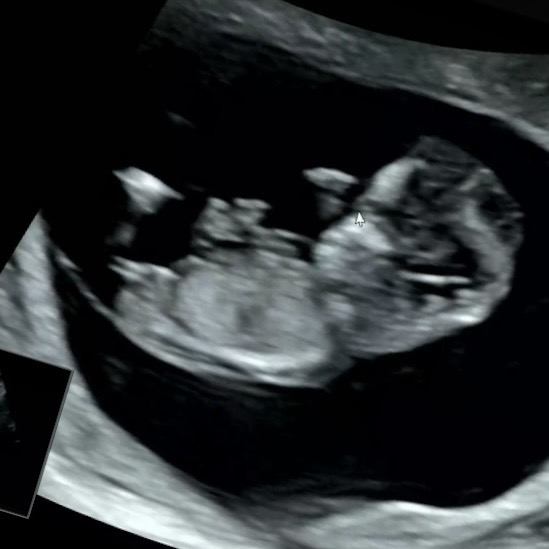

11주5일 각도법 고수님들!!!

각도법 고수님들 11주5일인데 각도법으로 딸일까요-? 아들일까요-?